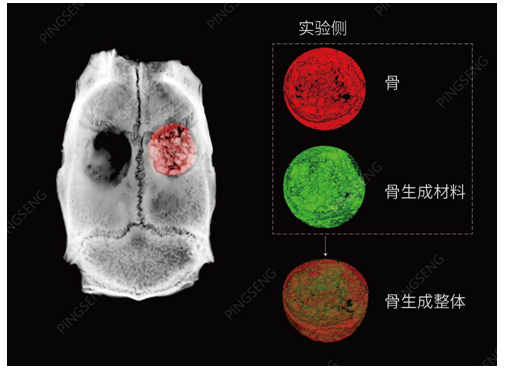

骨再生材料研究

有关材料植入物的骨骼研究中,通常的目标是检查骨整合,即植入物周围的骨骼状态。显微CT可以提供植入物和周围骨骼的3D图像数据,并提供相关分析。